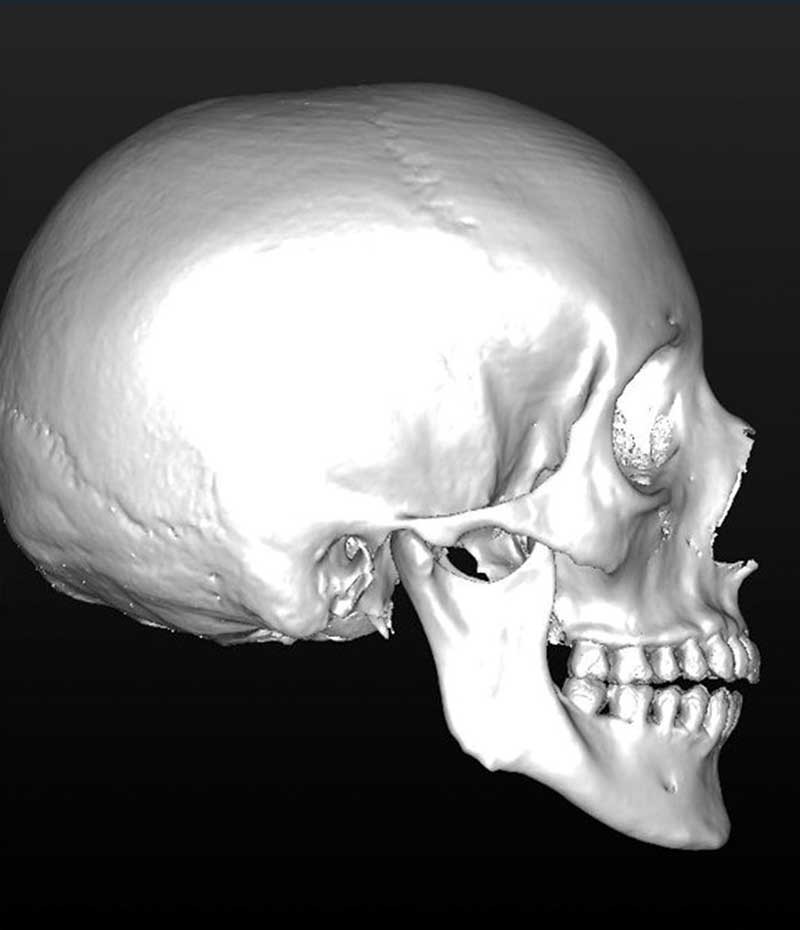

La mandibule est maintenue stable pendant l’examen. Sa position varie selon la typologie du patient. En cas de normo ou d’hyper-divergence, la mandibule est stabilisée en relation centrée (fig. 1).